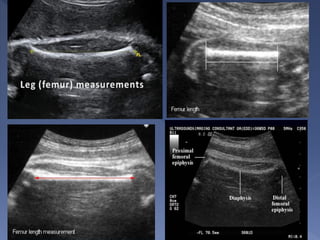

 serves as a monitor for growth of the long

bones.

 The femoral shaft is seen as a slightly

curved, echogenic structure that produces

an acoustic shadow

 The longest dimension of the femoral shaft is

measured for the FL

 The transducer should be aligned along the

long axis of the bone should include

measurement of the entire diaphysis.

 The femoral epiphysis, seen as a spike on

one end of the femoral shaft, is not

included in the measurement.

 The measurement is most accurate when

the femur is perpendicular to the US beam

 Measures the longest bone in the body and

reflects the longitudinal growth of the fetus

 The use of FL in dating is similar to the BPD,

and is not superior unless a good plane for

the BPD cannot be obtained or that the

head has an abnormal shape.

 Similar to the BPD, dating using the FL

should be done as early as is feasible.

 The FL is a mandatory measurement

 the FL has a very important function of

excluding dwarfism in the fetus.

 The extension to the greater trochanter and

the head of femur should not be included

 The measurement is also consider

inaccurate when the femur image is at an

angle of over 30 degrees to the horizontal.

 measurement of the FL is considered

accurate only when the image shows

two blunted ends.

 Appropriate plane

› U/S beam should be perpendicular to the bone

› Measurement is made along the femur diaphysis

› Exclude the distal femoral diaphysis